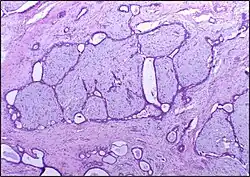

![]() | Follicular lymphoma | Micrograph showing a small B-cell lymphoma compatible with follicular lymphoma. H&E stain. | Category: Histopathology of follicular lymphoma | Follicular lymphoma |